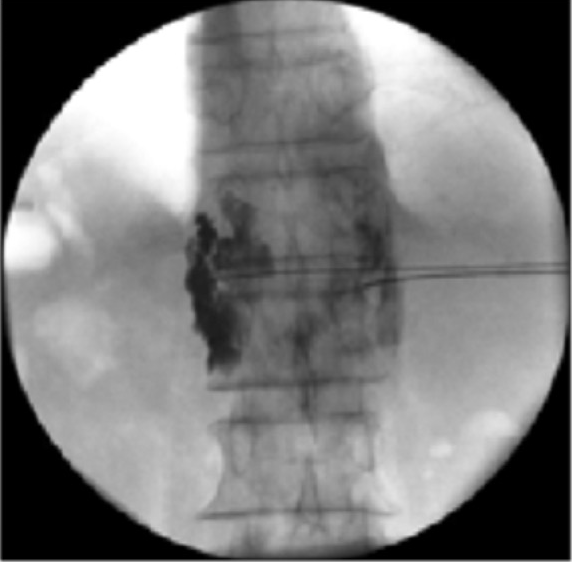

Chemical Neurolysis Spine specialist doctor in surat Spine

From spinepaincaresurat.com

Chemical Neurolysis spine specialist doctor in Surat Dr.shishir What Is Medical Term Neurolysis Chemical neurolysis is the application of a chemical agent directly to a nerve or motor point to intentionally interfere with. Release of a nerve sheath by cutting it longitudinally. Relief of tension upon a. Neurolysis is a surgical procedure that removes scar tissue from around and sometimes from within the nerve to improve its function. Operative breaking up of perineural. What Is Medical Term Neurolysis.

Chemical Neurolysis Spine specialist doctor in surat Spine What Is Medical Term Neurolysis Operative breaking up of perineural adhesions. Chemical neurolysis is the application of a chemical agent directly to a nerve or motor point to intentionally interfere with. Neurolysis is a surgical procedure that removes scar tissue from around and sometimes from within the nerve to improve its function. Direct nerve repair or primary. How to use neurolysis in a sentence. Neurolysis. What Is Medical Term Neurolysis.